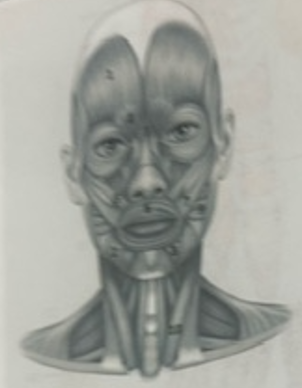

What muscle is 1?

Frontalis

What muscle is 2?

Depressor anguli oris

What muscle is 3?

Depressor labili inferioris

What muscle is 4?

Corrugator supercili

What muscle is 5?

Orbicularis oris

What muscle is 6?

Zygomaticus minor

What muscle is 7?

Zygomaticus major

What muscle is 9?

Buccinator

What muscle is 10?

Sternocleidmastoid

What muscle is 11?

Temporalis

What muscle is 12?

Masseter

What muscle is 13?

Risorius